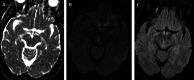

Stroke can present with unique neurologic symptoms, which can be used to help determine the location of the stroke. Internuclear ophthalmoparesis (INO), also known as internuclearophthalmoplegia, is a distinct gaze abnormality with impaired horizontal eye movements with compromised adduction of the affected eye, and abduction nystagmus of the contralateral eye. Infarcts involving the medial longitudinal fasciculus in either the pons or midbrain can result in INO. We present two cases of midbrain ischemic stroke, which presented as isolated INO. The midbrain has a unique and intricate vascular supply including branches from the basilar, superior cerebellar, posterior cerebral, posterior communicating, anterior choroidal, and posterior choroidal arteries, which is reviewed. Infarcts involving the paramedian midbrain, which is supplied by short circumferential arteries and penetrating branches arising from the posterior cerebral artery and superior cerebellar artery, can result in INO.